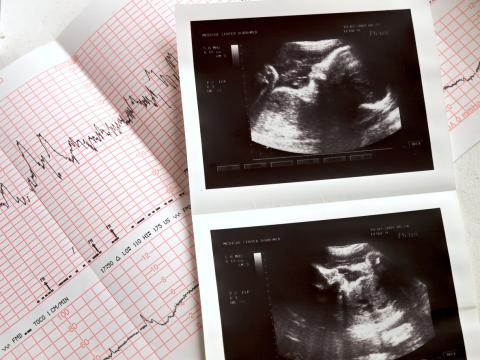

During normal fetal circulation the fetus receives oxygen directly from the mother through the placenta. Blood enters the fetus’s right... Read More